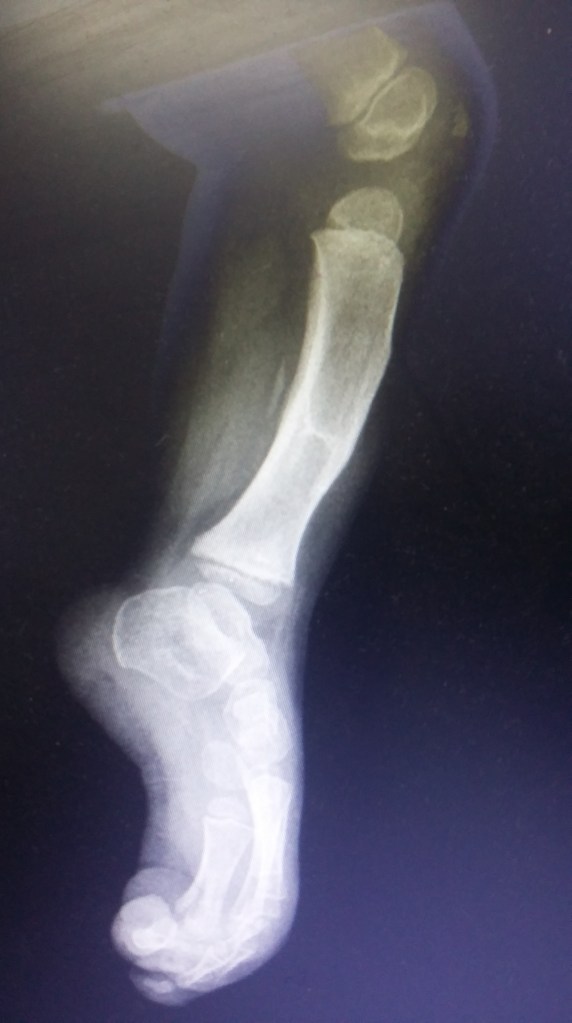

Infección y deformidad en tobillo y pie mas acortamiento óseo de pierna

Luego de varios años y cirugías sufridas por un accidente en moto, mi pie y pierna presentaban una gran deformidad asociada a una osteomielitis .

En mi provincia Chubut no podían tratarme más y solo me ofrecían la amputación

Tras viajar a BS AS y tener una consulta personal con el Dr Dratewka y Equipo en Cotram me realizaron estudios de imágenes y explicaron las posibilidades de Reconstrucción y evitar así la amputación

No solo trataron mi infección sino que corrigieron mi pie y me alargaron la pierna para poder caminar sin dificultades